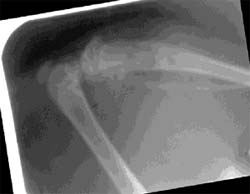

La Figura 2, muestra el nivel de radiopacidad de radiografías tomadas a las muestras en los (T) experimentales. Cabe destacar que el número mas alto indica mayor radioluminosidad. Se observa claramente el incremento de material radiopaco a medida que pasa el tiempo, llegando a los 30 días a no distinguirse claramente, el lugar de la incisión. Esta situación se observa en todos los casos estudiados Las Rx muestran diferencias estadísticamente significativas (p=0,05) entre los dos grupos, observándose formación ósea en cuanto a volumen.

| Problema día 7. | Image Plus día 7. | ||||

| Problema día 30. | Image Plus día 30. | ||||

Estudios experimentales previos (27) han demostrado que la aplicación tópica de una dosis de 200 ?g de alendronato colocado en el sitio de la cirugía mucoperióstica reduce la cantidad total de la resorción del hueso alveolar. Diversos autores han demostraron también el efecto de diferentes bisfosfonatos, administrados sistémica o localmente, en la recuperación de los niveles óseos posterior a la cirugía mucoperióstica utilizando el mismo método de evaluación. (28-29) En concordancia, el presente estudio ha demostrado un significado incremento del material radiopaco del hueso en los animales que recibieron alendronato, en comparación con el grupo que sólo recibió buffer, llegando a los 30 días a no distinguirse claramente el lugar de la incisión. La efectividad del tratamiento de alendronato, en dosis de 0,5 mg/Kg de peso corporal, es medible en los diversos cambios producidos a nivel de la pérdida ósea produciéndose un incremento en el porcentaje de hueso con características de normalidad. Cuando el alendronato fue aplicado cercano al sitio de la cirugía, la dosis utilizada como lo indica el fabricante fue significantemente efectiva (p<0,001) en incrementar los niveles óseos. También pudimos observar que la administración subcutánea es significativamente efectiva en los tiempos quirúrgicos, porque la absorción de la droga en la circulación y la rápida distribución hacia el tejido óseo es buena, a pesar de la gran avidez de la droga el resto de tejido duro circundante. Estudios previos, que usaron alendronato marcado pudieron demostrar que el mismo se absorbe en un 10% a nivel de la cirugía realizada a nivel alveolar. (29)